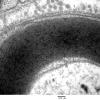

PERIPHERAL NEUROPATHY

2 NORMAL AXON (2)